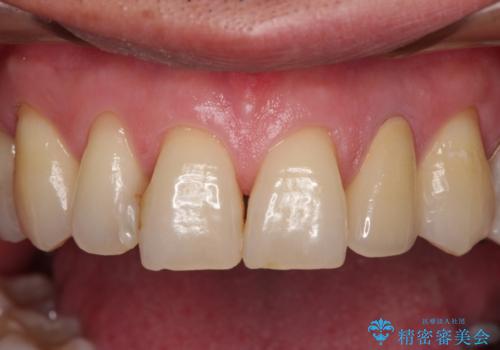

根管治療の土台のまま放置してしまった前歯 オールセラミッククラウンによる補綴治療

土台の状態は良好であったため、仮歯に置き換えた上でオールセラミッククラウンにて補綴治療を行うこととしました。

見た目の改善はもちろんですが、ものが挟まらなくなったり、舌触りが良くなったりと、口腔内の状態が改善されました。